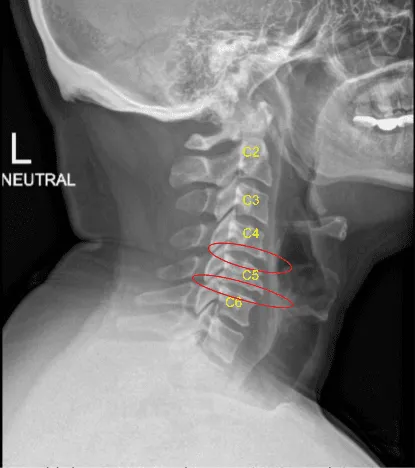

A pleasant patient who was involved in a car crash and subsequently developed neck pain. They had lots of conservative treatments, but ultimately failed, and developed myelopathy with correlated imaging findings from C4 to C6. Therefore, we offered surgery. The patient gave informed consent, understanding all of the risks, benefits, and alternatives to surgery.

Mild degenerative changes C4-C5 and C5-C6